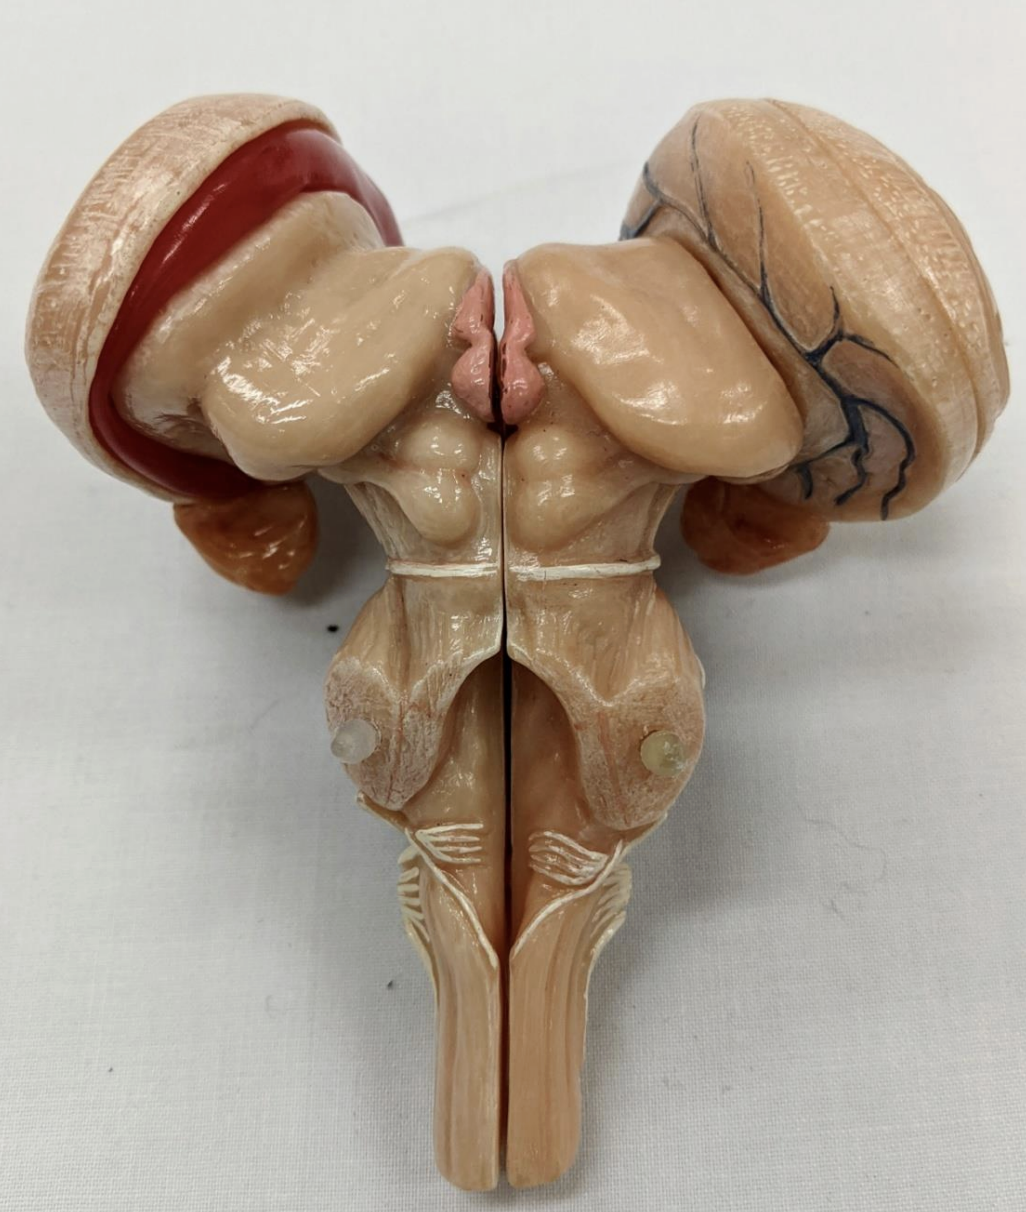

Anterior median fissure

Posterior median sulcus

Posterolateral

Anterolateral sulci

Diencepathon

Thalamus

Interthalamic mass

Striae medullaris thalami

Habenular nucleus

Pineal gland

Hypothalamus

Cerebellum

Anterior lobe of cerebellum

Horizontal fissure

Posterior lobe of cerebellum

Cerebellar tonsils

Posterolateral fissure

Superior medullary velum

Arbor vitae

Folia

Amygdala

Mammillary bodies